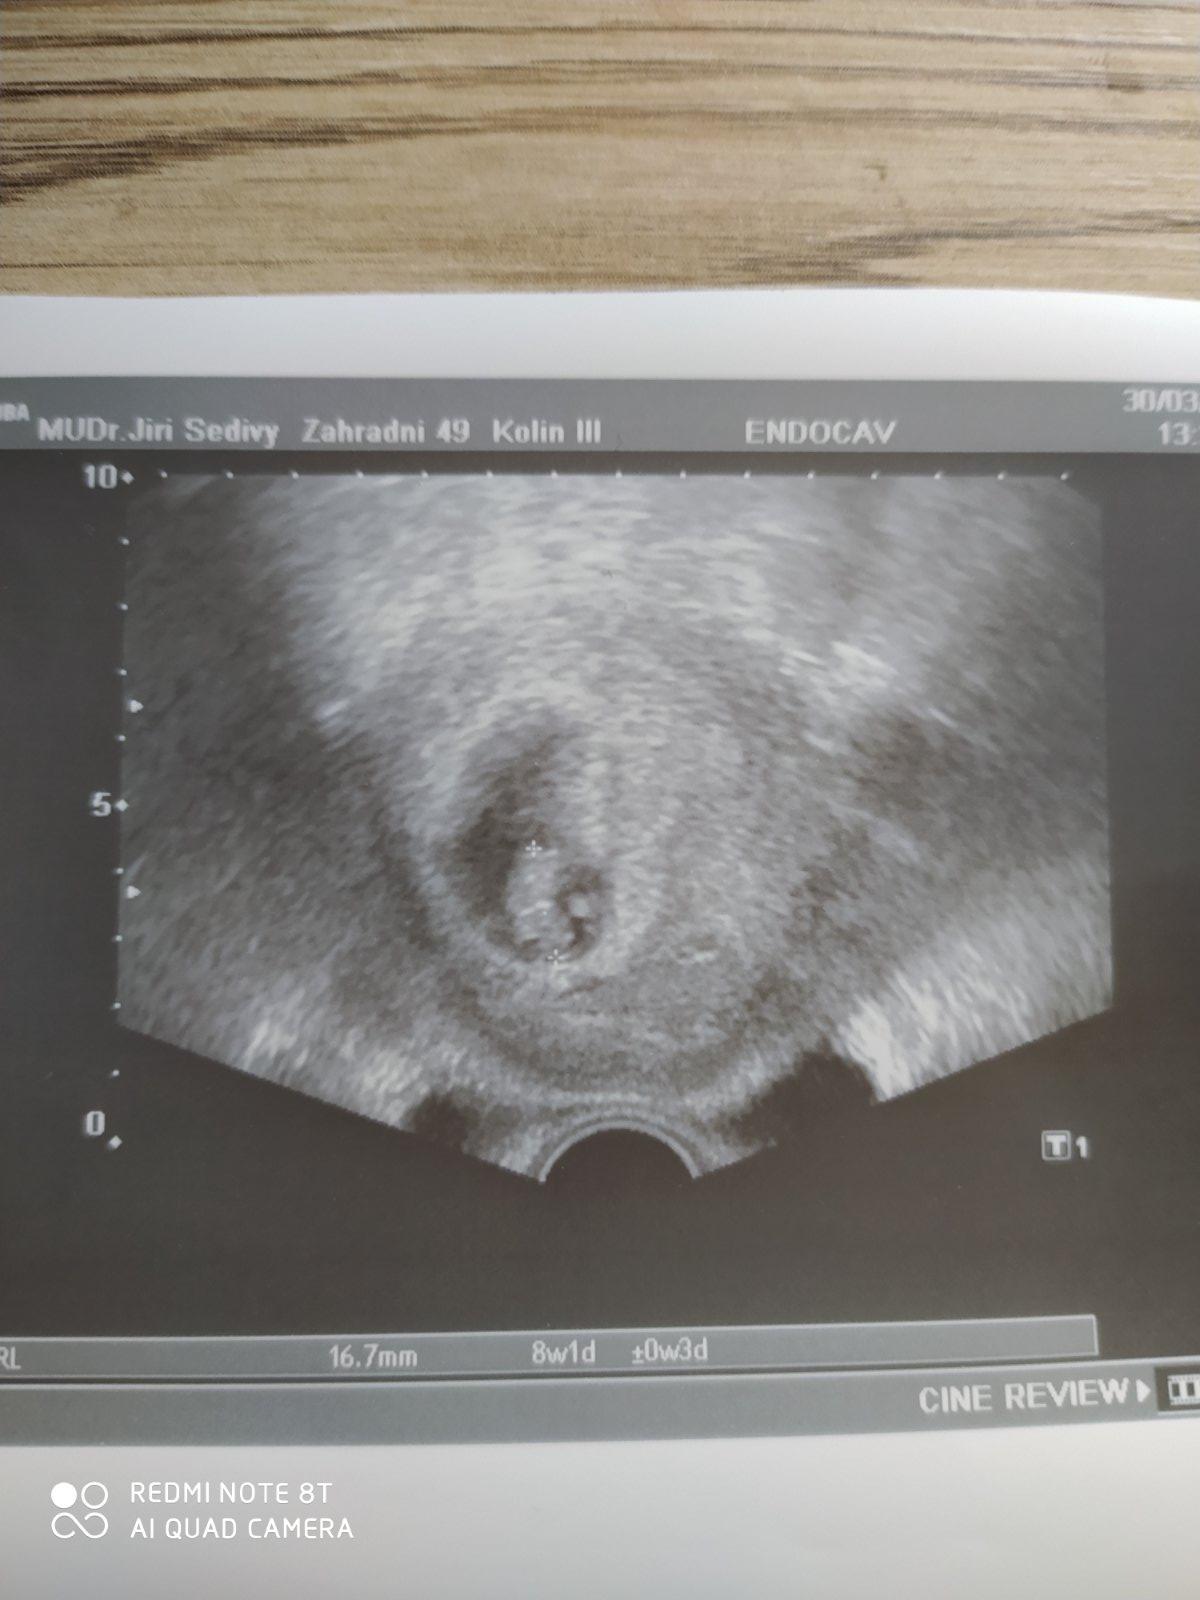

@levandulka_fialova pokud otěhotním, tak si ten utz na začátku taky vydupu. Klidně zaplatím, ale už nedovolím, abych šla v 7tt a pak až ve 12tt. Na ZT se tak mohlo přijít dřív a hlavně když je vše ok, tak nás to uklidní.

@levandulka_fialova jinak v předchozím těhotenství jsem taky chodila častěji a utz na každé kontrole. Ale teď dr.usoudila, že když už bilo srdíčko, že není třeba už zase chodit tak brzy